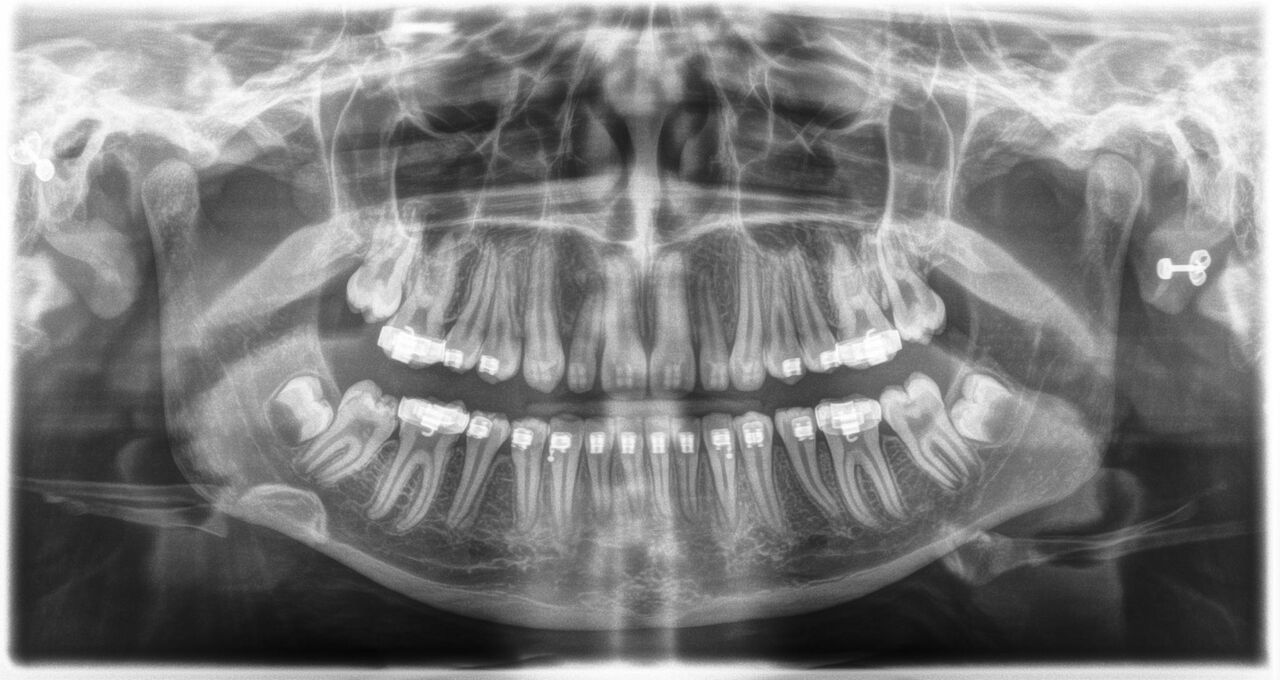

The sound 2D X-ray unit providing a smooth entrance into the world of digital imaging. Thanks to CsI sensor technology and its easy-to-use interface, you are ensured reliable diagnostics every time. The cephalometric option also makes the Orthophos E a reliable partner for orthodontics. Enrich your practice with a wide range of services that are only possible with digital imaging.

Orthophos E has two integrated light localizers to facilitate ideal positioning in the sharp layer. The motorized forehead and temple supports gently fix the patient’s head in place and provide additional support to prevent motion blurring.